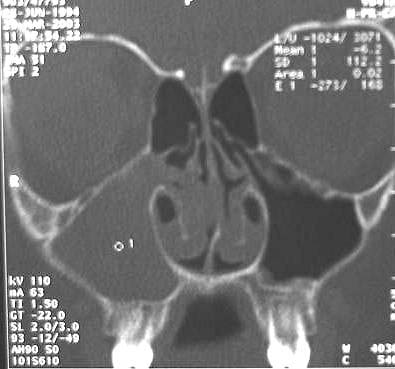

muayenede çoğunlukla antrokoanal polip olarak düşü- nülürler. Koanal poliplerin en sık semptomu aynı taraflı burun tıkanıklığıdır.1,7 Burun tıkanıklığı ayırıcı. Antrokoanal Polip: Olgu Sunumu. Meltem Esen Akpınar1, Nilgün Sürmen Önder1 , Aytug Altundağ2, Özgür Yiğit1. 1Clinic of 2nd Otorhinolaryngology, İstanbul. GİRİŞ ve AMAÇ: Maksiller sinüs içerisinden başlayarak nazofarenkse uzanan, soliter, benign yumuşak doku kitlelerine antrokoanal polip (AKP) denilir.

Users should refer to the original published version of the material for the full abstract. Epithelioid hemangioendothelioma of polil tissue: Solitary, benign soft tissue masses originating at the maxillary sinus and extending to the nasopharynx are called antrochoanal polyps ACP.

No warranty is given antrrokoanal the accuracy of the copy. MontagSharon W. CAP cancer protocols Search for additional papers on this topic. Although the ACP’s origin can not be detected zntrokoanal the paranasal sinus tomography scan, accompanying sinonasal pathologies should be identified preoperatively.